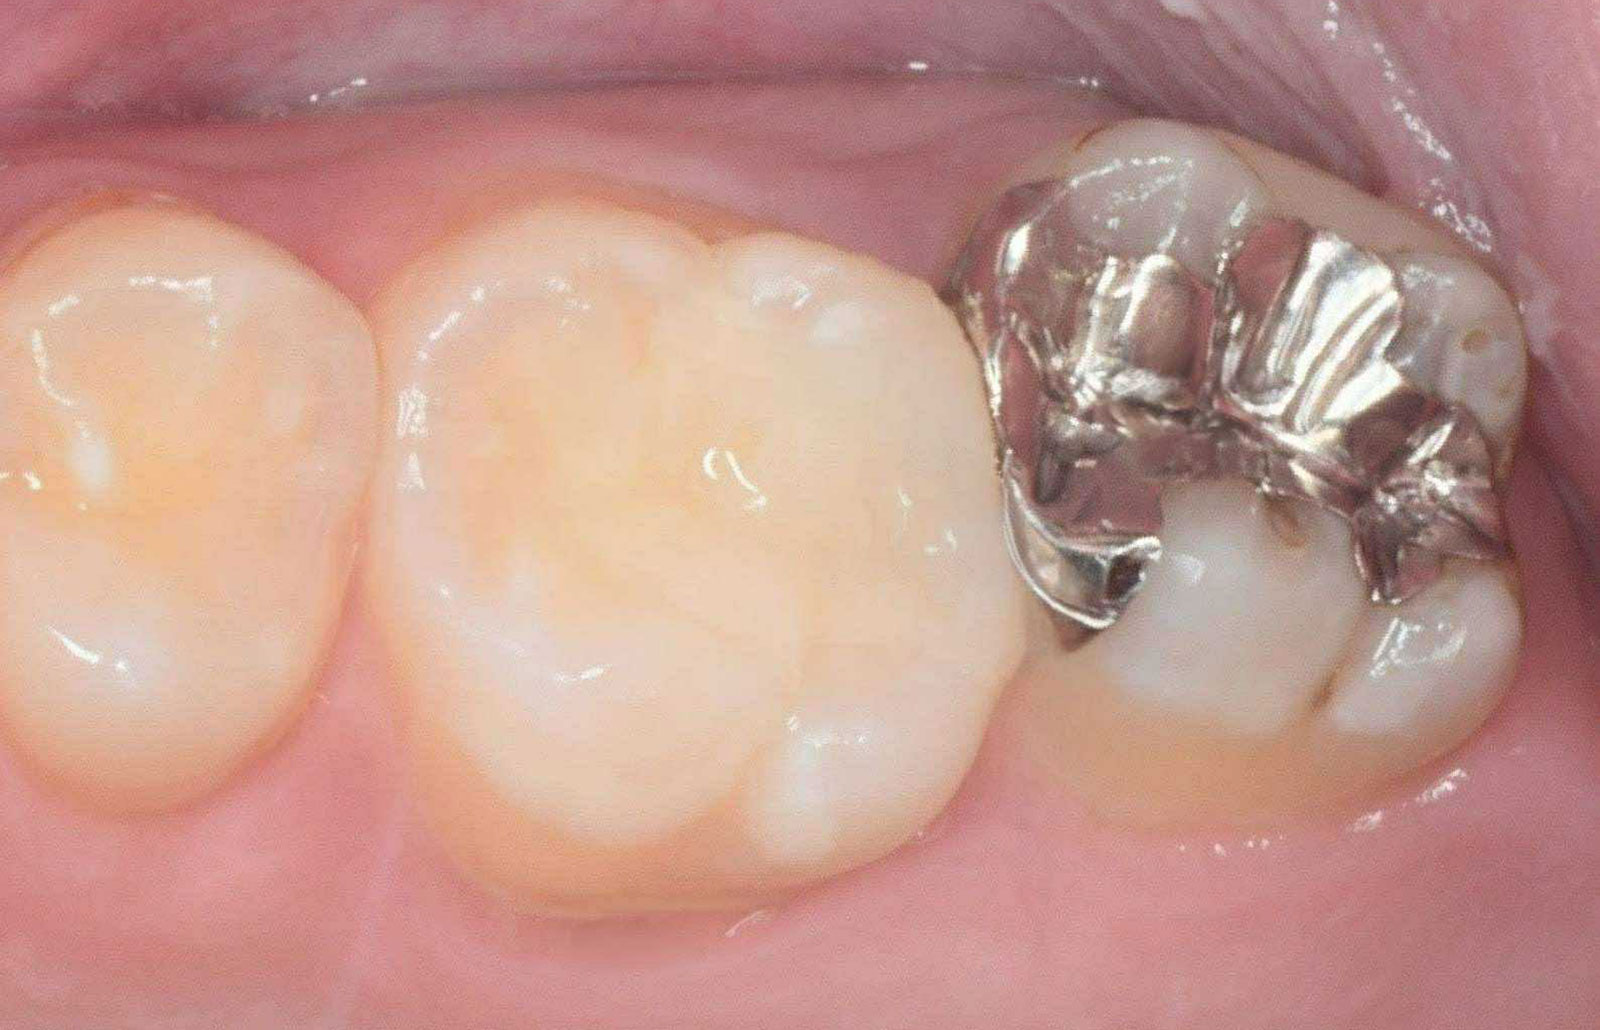

被せ物の製作は歯科医師ではなく、歯科技工士が担当します。

当院ではBright dental artsの代表・伊藤氏に依頼し、クオリティの高い補綴物を患者様へ提供します。